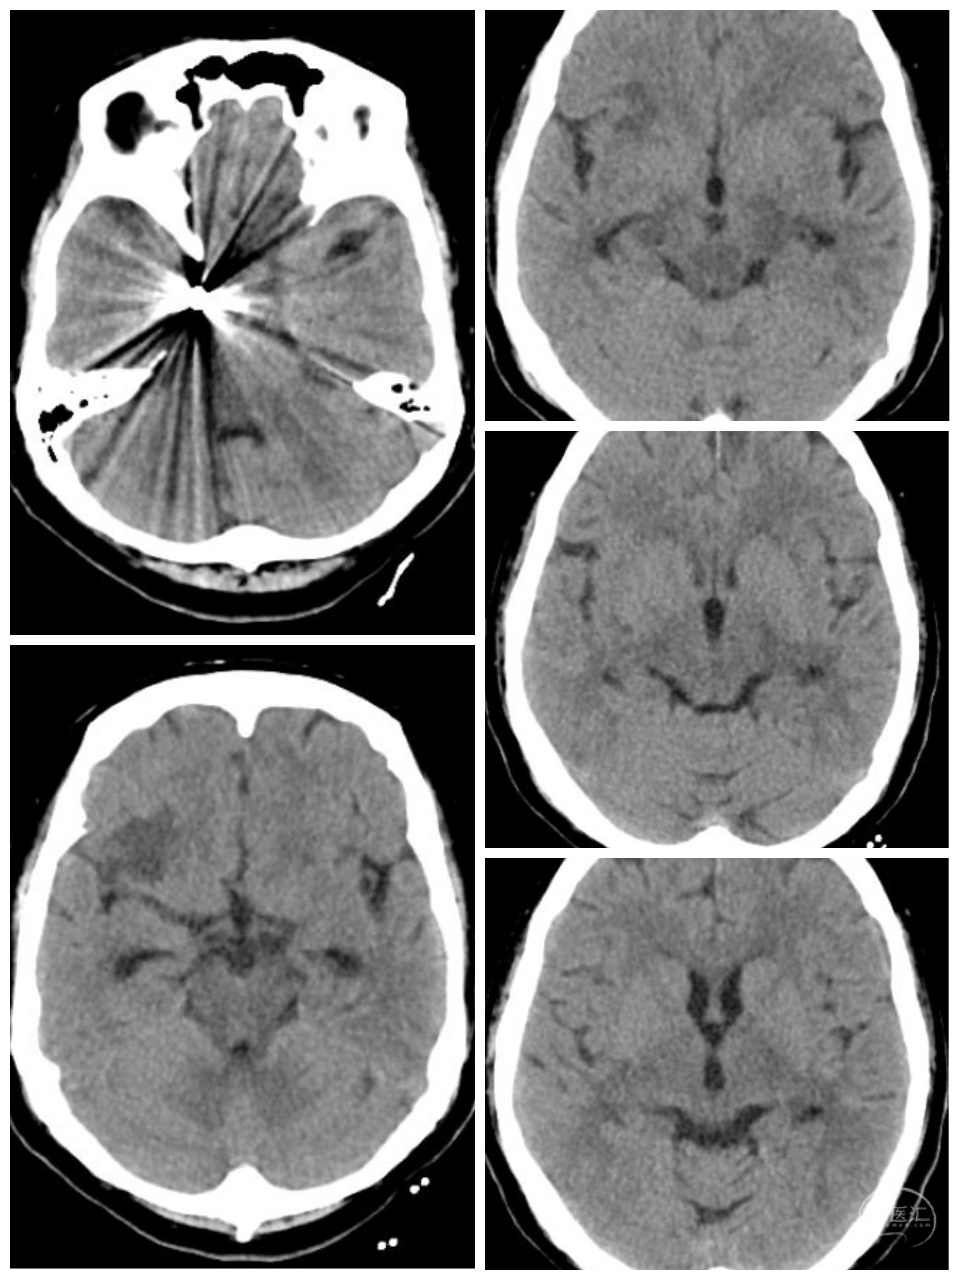

女性,66岁,突发剧烈头痛2小时。Hunt-Hess二级。

术后第二天CT:未见异常,术后一周顺利出院。